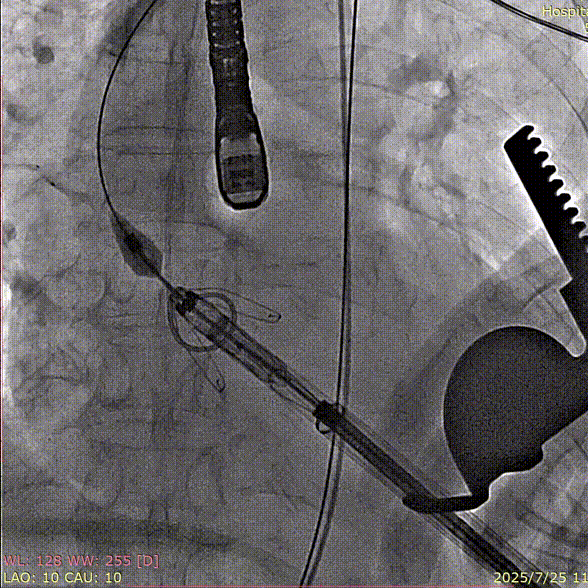

术中回顾及效果

在DSA和超声引导下,手术团队高效精准的完成瓣膜定位、释放与功能评估。手术过程顺利,器械用时7分钟。术后造影和超声提示瓣膜稳定性良好,无瓣周漏,平均主动脉跨瓣压差6mmHg。

输送器经左室跨瓣

夹持件顺利入窦

瓣膜释放、解离

术后造影